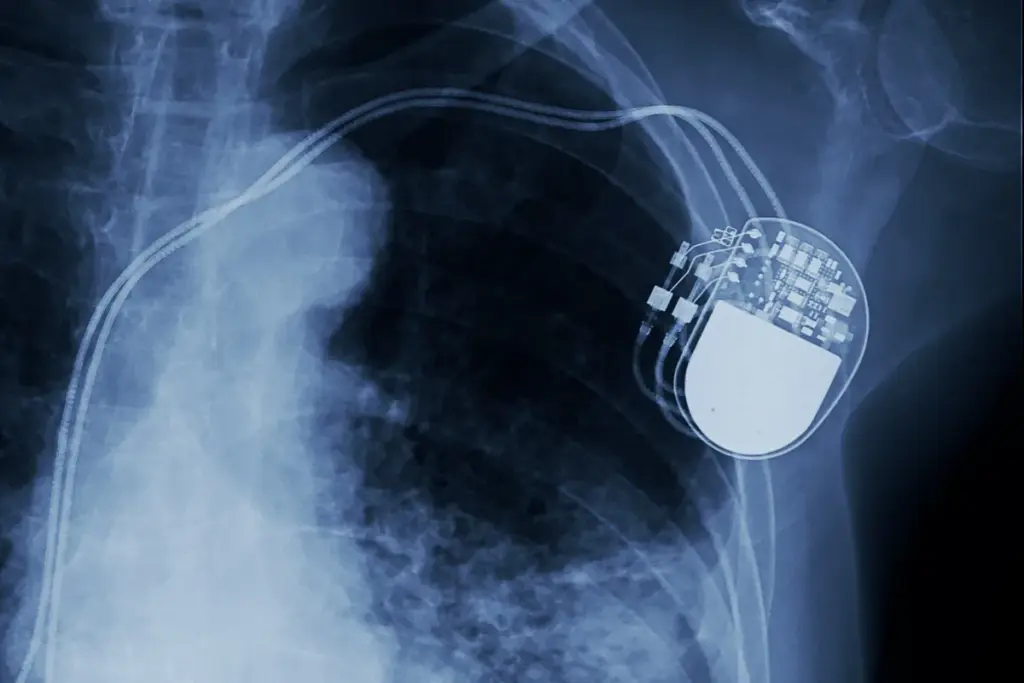

Knowing how your cardiac pacemaker works is key to keeping your heart healthy. It’s a small device that helps control your heartbeat by sending electrical signals.

How a Pacemaker Functions in Your Heart

A pacemaker sends electrical signals to your heart to keep it beating regularly. This is vital for people with irregular heartbeats. It has two main parts: the pulse generator and the leads.

The pulse generator watches your heart’s rhythm and sends signals when needed. This keeps your heartbeat steady, improving your heart’s function and easing symptoms of irregular heartbeats.